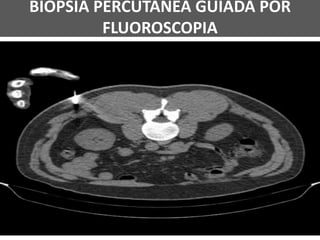

BIÓPSIA PERCUTÂNEA GUIADA POR TC

BIÓPSIA PERCUTÂNEA GUIADA POR

FLUOROSCOPIA